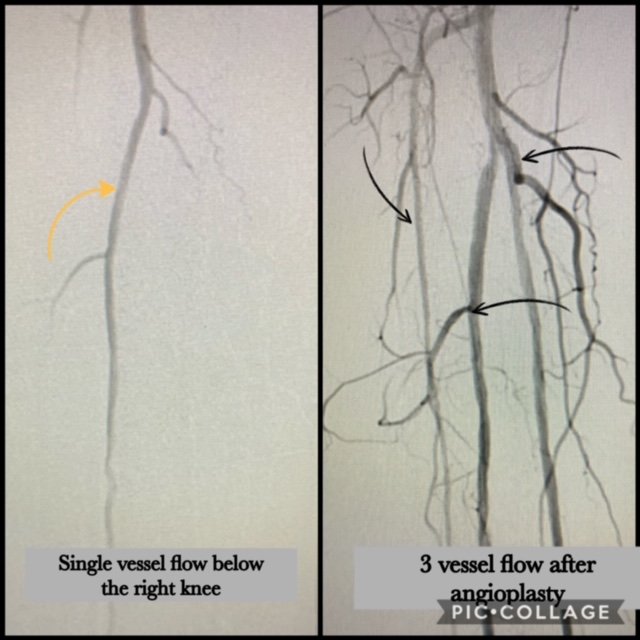

pad treatment

Case of the Day – Treating Peripheral Arterial Disease

Our AHV team led by Dr. M. Bisharat managed to perform this complex case safely and successfully in less than an hour.